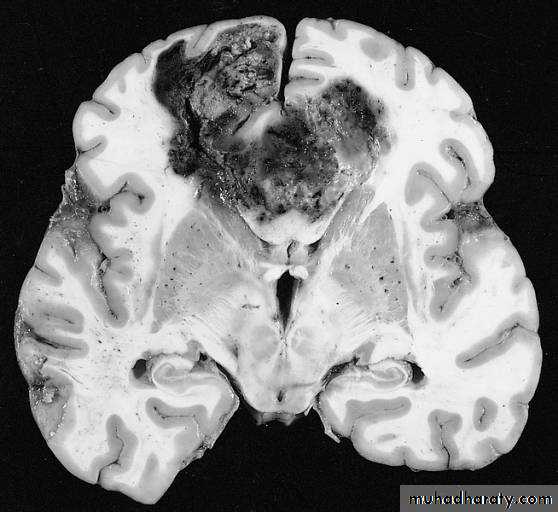

GLIOBLASTOMA MULTIFORMI